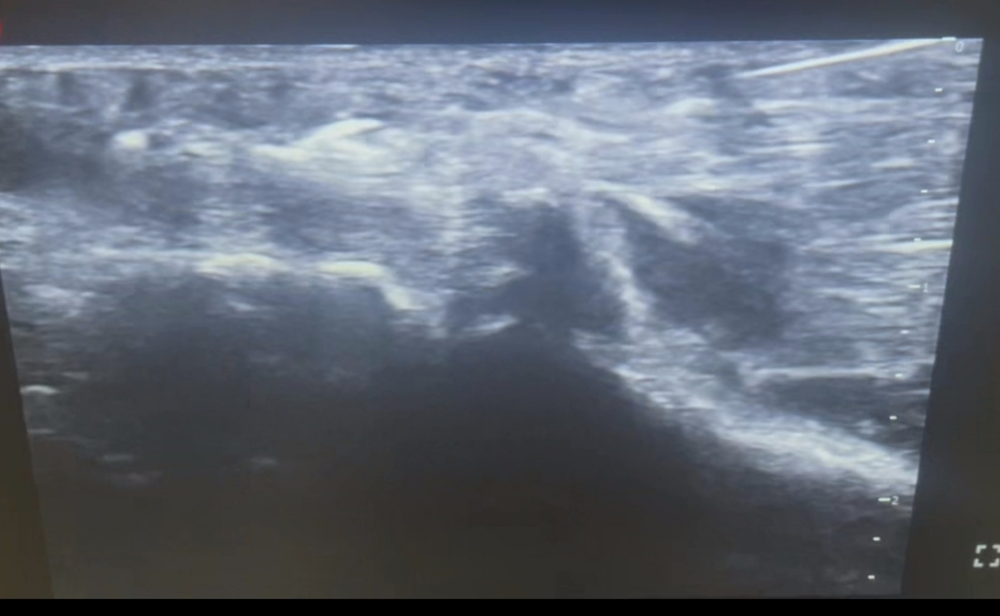

邹宇聪主任接诊后,仔细评估了A先生的病情。通过超声检查,清晰地看到:增厚的腱鞘、膨大的肌腱、卡压的位置——病灶一目了然。针对A先生的情况,邹主任决定采用“超声引导下小针刀治疗”——一项微创、可视化的精准治疗技术。

超声引导下小针刀治疗,是将传统小针刀的“松解”作用与超声的“可视化”技术深度结合的一种精准微创治疗技术。简单来说,它让医生在操作时,眼睛能“看穿”皮肤,实时避开血管、神经,精准到达病灶,既保留了传统针刀松解粘连、减压镇痛的效果,又大大提升了安全性与疗效。

邹宇聪主任介绍,该治疗超声实时成像可清晰显示针刀路径及靶点组织,避免误伤神经血管,提升操作安全性。适用于肌腱炎、腱鞘炎、筋膜炎、关节囊挛缩等多种软组织疾病,涵盖颈肩腰腿痛、狭窄性腱鞘炎、足底筋膜炎、关节软组织损伤等常见病症。

松解完成后,邹主任再次用超声扫查,确认腱鞘卡压处已充分松解,肌腱滑动顺畅。随后让A先生主动活动手指,原活动受限的拇指屈伸范围明显改善,屈伸时未再出现弹响及卡顿感。术后仅以创可贴覆盖针眼,无需缝合,嘱其24小时内保持创口干燥。